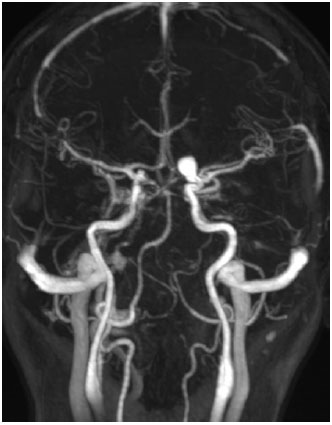

The patient returned 45 days later reporting the onset of dyschromatopsia. The ophthalmologic findings did not differ from those recorded at her initial visit. A nuclear magnetic resonance examination was requested and showed an internal carotid aneurysm of approximately 3.5 mm × 6.5 mm near the emergence of the ophthalmic artery. This aneurysm compressed the optic nerve (Figure 4). The patient was referred to a neurosurgeon and underwent endovascular aneurysm occlusion. Three months after surgery, she reported improvement in the headache symptoms, but a visual field test revealed a diffuse loss of sensitivity.